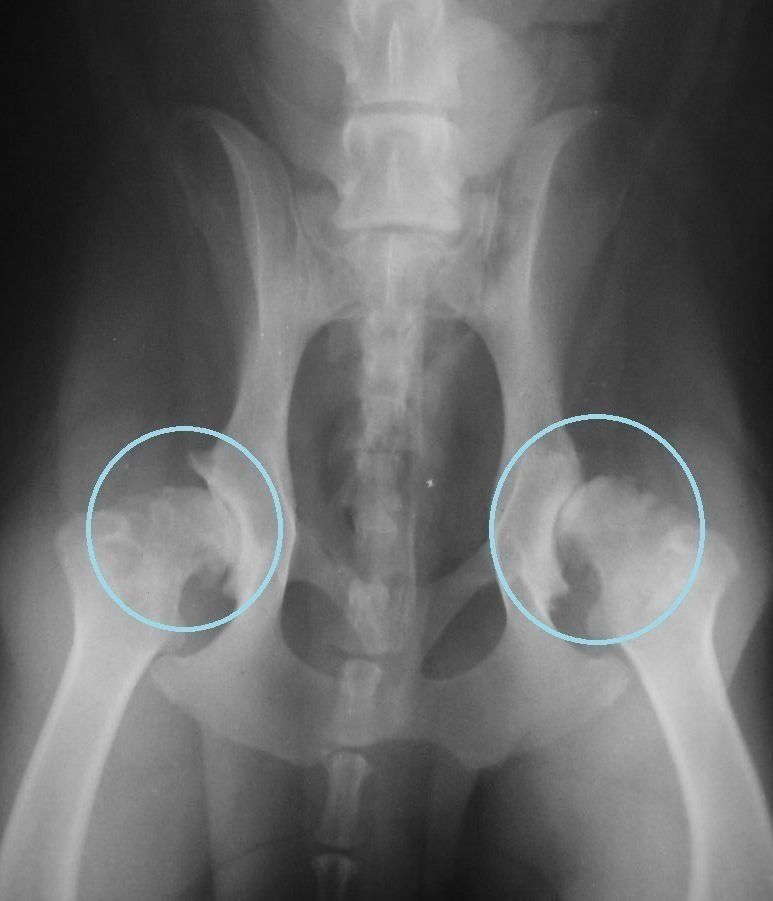

心当たりがあった場合、もしかすると股関節形成不全(こかんせつけいせいふぜん)という病気かもしれません。これは、股関節が正しい形につくられず、関節が変形したり、歩くたびに痛みが出るといったさまざまな症状を引き起こす病気です。とくに発育過程である子犬期に症状が出やすく、重症化すると歩けなくなることも!

お尻を大きくフリフリと振りながら歩くなど、特徴のある歩き方をするのが発見のポイントですが、「うちのコの歩き方、かわいい♥」など、飼い主さんがクセや個性と勘違いしやすいので、見逃してしまいがちです。